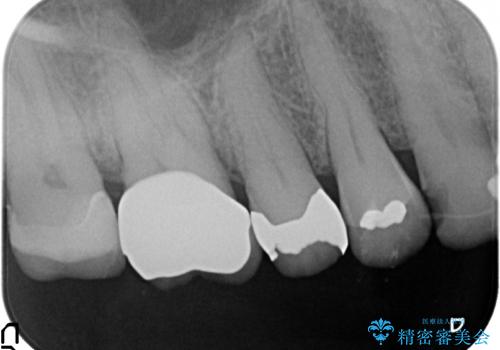

- 冷たいものがしみる右上の奥歯を治療して欲しいといらっしゃった方の症例です。

右上6,7の金歯を外したところ、虫歯が歯茎より深い位置まで進行していたため歯周外科を行いました。

その後歯茎の回復を待ち、オールセラミッククラウンおよびセラミックインレーによる補綴・修復を行いました。